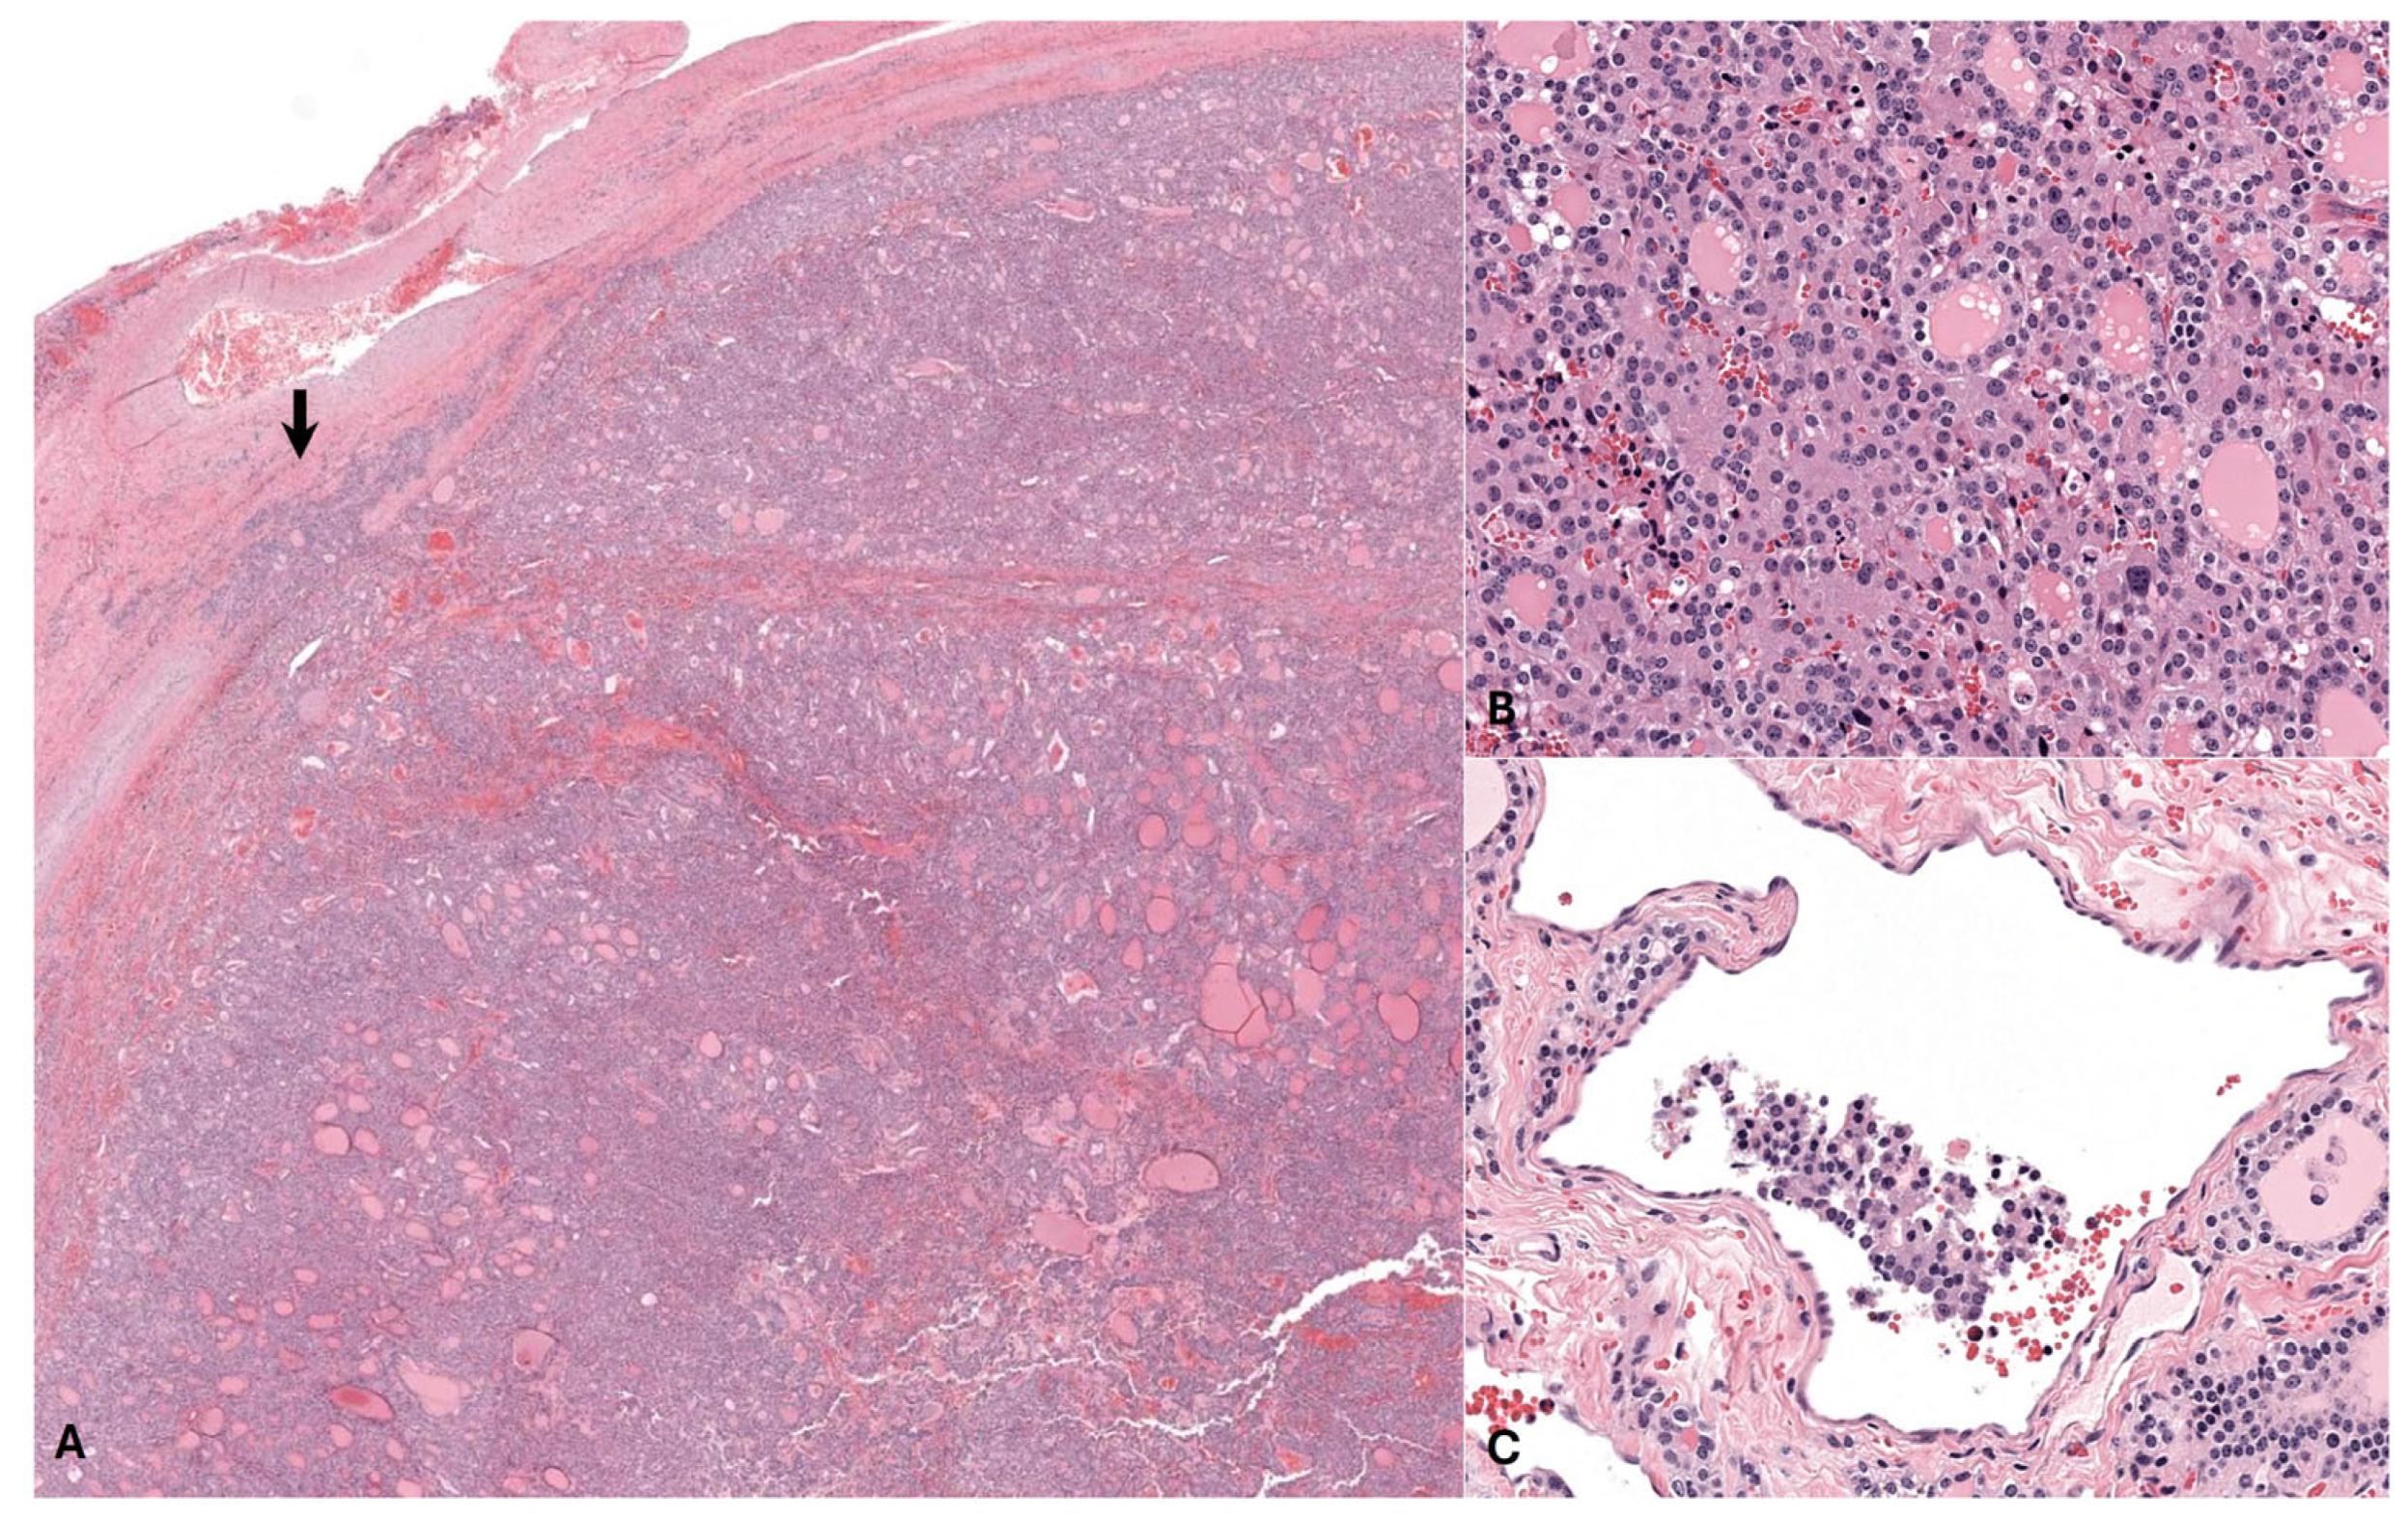

3.2. Histopathology